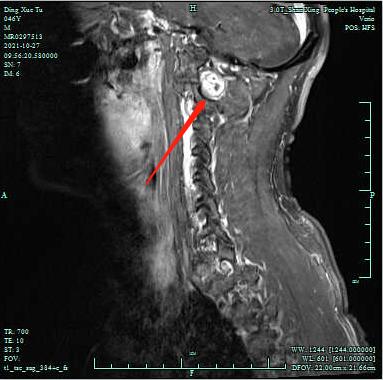

患者磁共振影像

近日,绍兴市人民医院神经外科团队结合多模式融合的3D打印技术非常成功地完成了一例高难度的高位颈椎神经鞘瘤微创手术。该患者的肿瘤位于颈1-2椎体水平的右侧椎管内,结合影像学信息可见局部高位的颈髓受压变形,且肿瘤位置靠近椎动脉及周边的重要神经血管,摘除难度非常高。

患者肿瘤累及的高位颈髓是调控人体呼吸和心跳的生命中枢,椎动脉是供应人体小脑和脑干的重要血管,对医生手术的精准度要求非常高,稍有不慎即会造成大出血,危及生命。最关键的问题是,二维影像无法精确了解肿瘤周围神经血管分布情况,为了能完整切除肿瘤的同时尽可能的保护颈髓和周围的血管神经不受损伤,医生将会用尽可能大的手术切口,磨开更多的椎体以暴露肿瘤。而过多地磨除椎体势必将严重影响椎体的稳定性。我们都知道,颈椎是人体活动度最大的椎体,一旦椎体骨质磨除过多导致术后稳定性变差,患者的颈部活动势必受到极大影响,手术风险程度尽显。